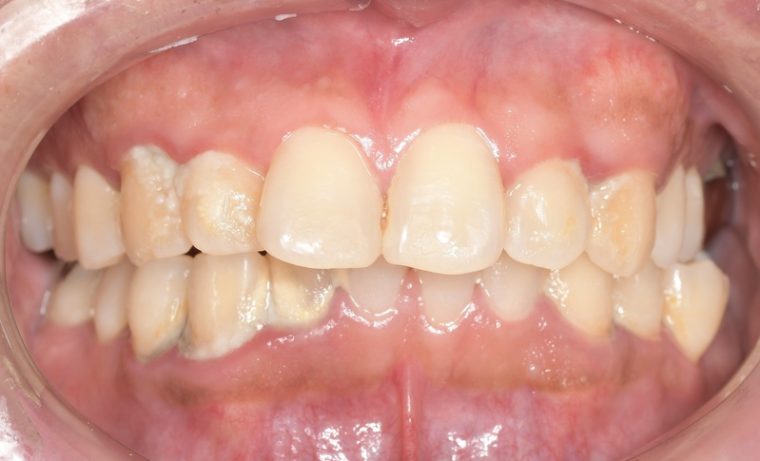

Before

症例

after

基本情報

年齢・性別 52歳・男性

主訴 主訴:久しぶりの歯医者なので歯石をとってほしい

治療部位:全顎

治療内容 1.歯磨き指導、歯肉縁上の歯石除去

2.歯磨きの確認、指導(磨けるようになるまで)

3.歯磨きの確認、指導、歯肉縁下の歯石除去(SRP)

4.PMTC

5.再評価、歯磨きの確認、指導

治療期間 1日

治療費 合計17,560円

・内訳

1、歯周基本検査・歯磨き指導、縁上スケーリング:1,800円

2、歯周精密検査・SRP(スケーリング・ルートプレーニング)、歯磨き指導:2,130円

3、SRP、歯磨き指導:3回(1,530円×3回)

4、PMTC、全顎再スケーリング、歯磨き指導:5,500円(自費診療)+1,260円

5、再評価(歯周精密検査)、歯磨き指導:2,280円

※PMTC以外、保険診療3割負担

(2023年5月現在現在)

リスク・副作用 ・毎日の歯磨きが不十分だと歯石を除去しても再度歯石がついてしまう

・最初は歯磨きのときに出血してくることがあるが、細菌が減って歯茎が引き締まってくると徐々に出血は落ち着いてくるため痛みがなければ辛抱強く磨いてもらう

・歯周病は時間をかけて静かに進行する病気なので、歯周病を治すにはそれなりに期間がかかる、すぐには治らない

・歯ぐきが引き締まると歯茎が下がり歯間に隙間ができる可能性がある

治療方針 一時的な治癒ではなく、将来的にこの治療が活かされるよう、患者さん自身である程度自己管理ができるようになることを目標とした

特記事項 ふつうのブラシと電動歯ブラシ使用(ブラウン丸型使)

歯間ブラシを1日1回は最低でも使って頂いた

担当者所見 あまり器用な方ではなかったため、決まったところがいつも磨けず奥歯に歯間ブラシがなかなか入れられませんでしたが、歯間ブラシのサイズを変えてみたり、内側から入れてみたりと試行錯誤してなんとかある程度磨けるようになりました。

その結果、出血が100%から7%へ激減することができました。

ただSRPをしただけではここまでの結果は出なかったと思います。

それほど日々のセルフケアが重要だということを再認識しました。

歯周ポケットが残っている部位、出血がある部位に関しては引き続き歯磨きを念入りに行なってもらう。